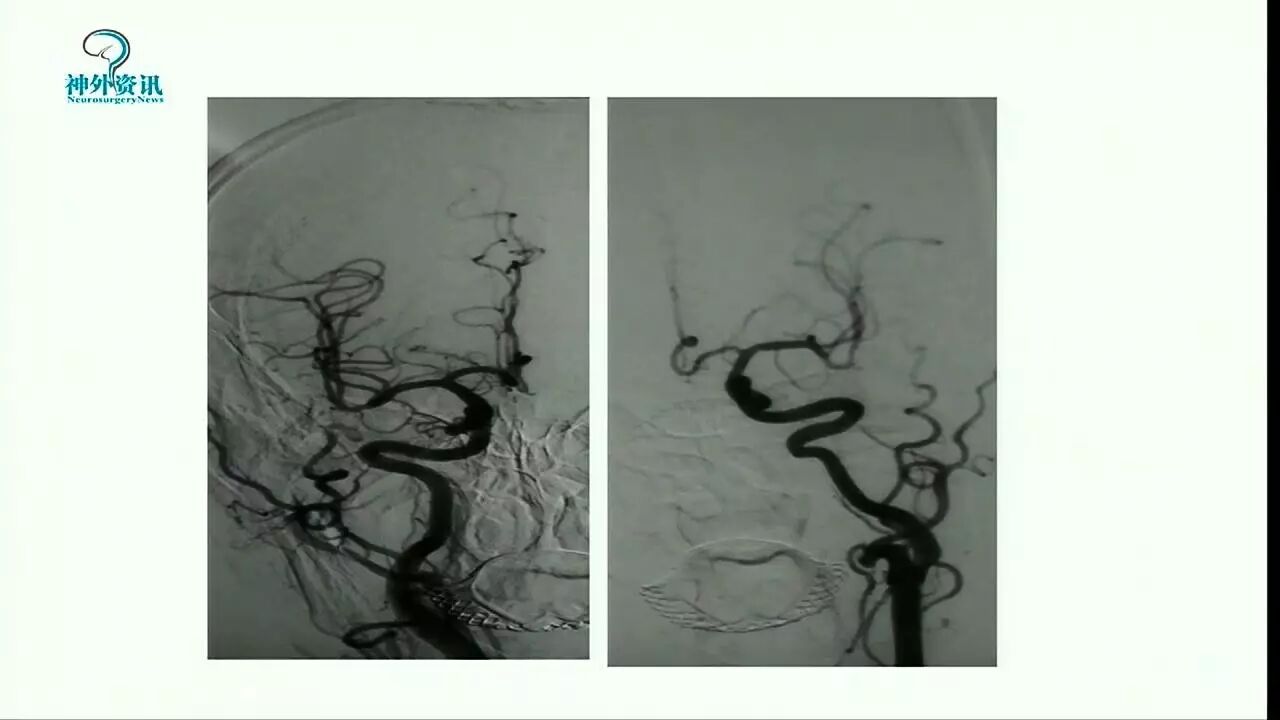

Enterprise支架在缺血性脑血管病中的应用